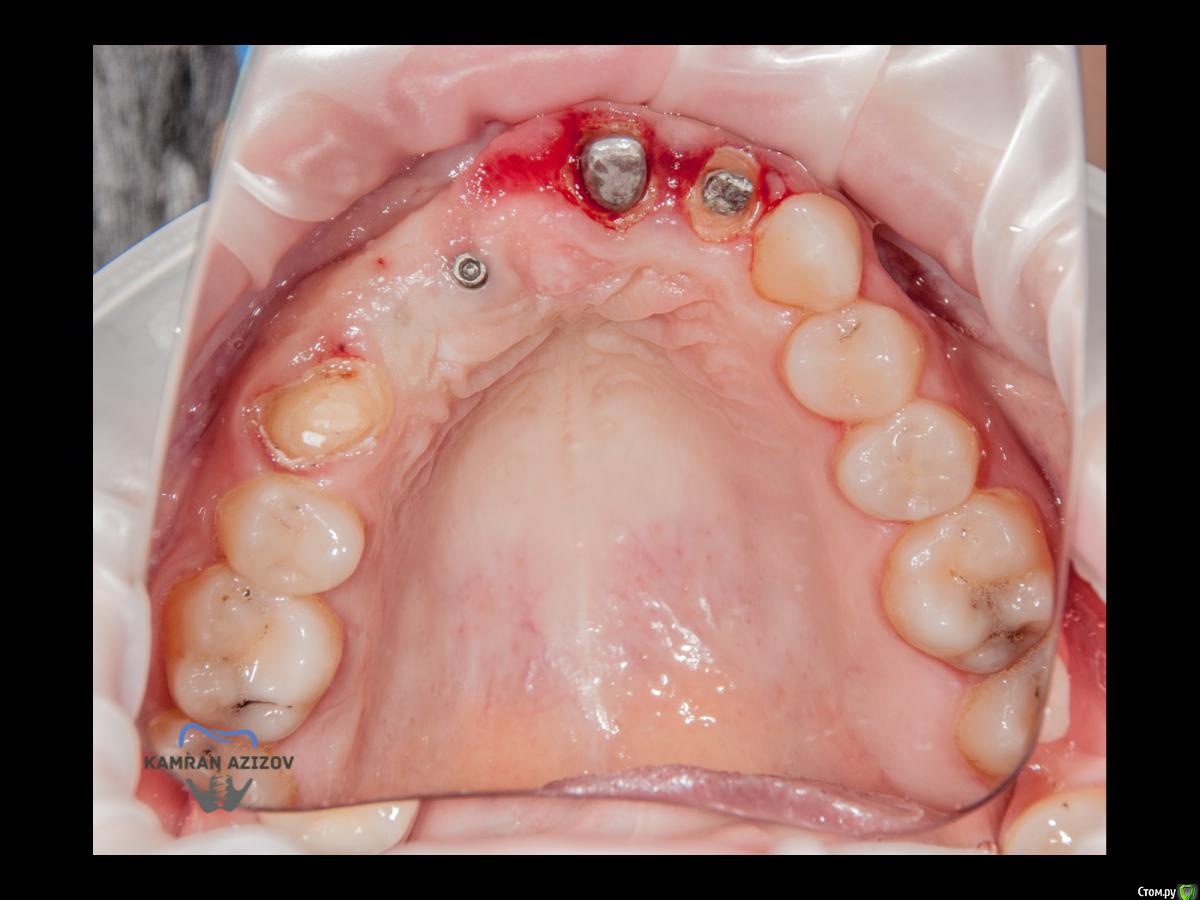

kamranchick Опубликовано 6 апреля, 2019 Поделиться Опубликовано 6 апреля, 2019 (изменено) Хай Гайсдавно ничего не комментировал и не выкладывал, что то настроения не было, да и муза не посещалаСитуация следующаяпришла пациентка, жалобы на неприятный запах из рта, сначала не понял что за хрень, ну как распилил мост понял че к чему... халтура.Ну и по кейсуУдаление клыка и 2ки, через 2 месяца навигация, имплантация + Шашлыки по карлоссу, смена формиков, временное протезирование. только мягкие ткани, Изменено 6 апреля, 2019 пользователем kamranchick 7 1 Ссылка на комментарий

Nazim_NV86 Опубликовано 7 апреля, 2019 Поделиться Опубликовано 7 апреля, 2019 Пятый Без пина шаблон не держался? Ссылка на комментарий

kamranchick Опубликовано 8 апреля, 2019 Автор Поделиться Опубликовано 8 апреля, 2019 Пятый Без пина шаблон не держался? держался) но сделали на всякий случай) Ссылка на комментарий